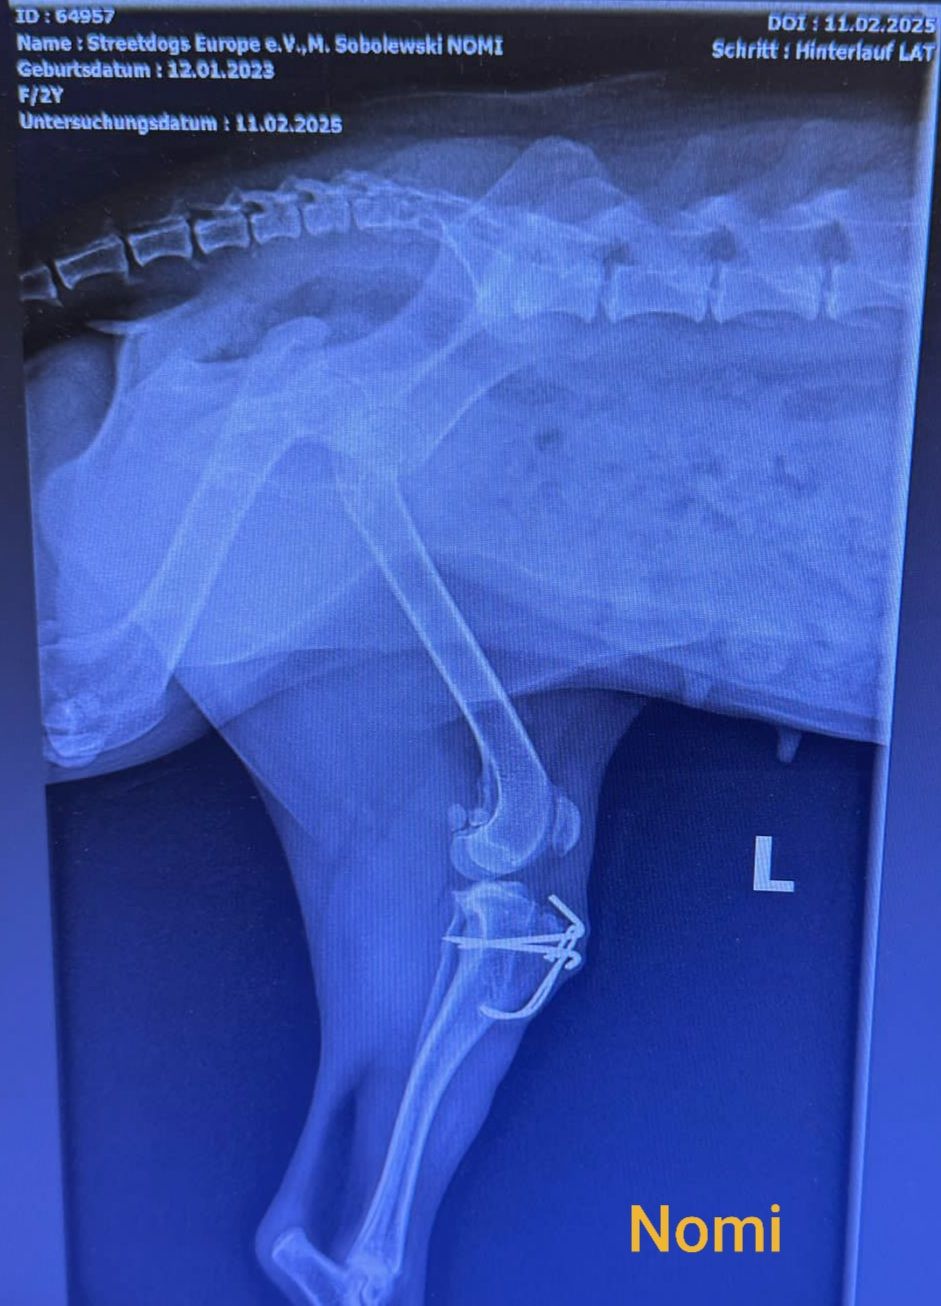

12.02.2025

Mir ist Dienstag was ganz blödes passiert…Ich weiß ja selber dass ich eine wilde Hummel bin, aber da hab ich doch etwas übertrieben! Ich habe mich sooo doll gefreut als Annette abends von der Arbeit nach Hause kam, da bin ich ihr ganz wild entgegen gelaufen und bin dabei mit meinem operierten Bein gegen die Treppenkante geknallt!

Das tat echt weh und ich habe mein Bein sicherheitshalber erst mal krumm zur Seite gestreckt… und auftreten konnte ich auch nicht mehr! Annette und Stefan waren total erschrocken und wir sind noch ganz schnell zum Doc nach Hattingen gefahren. Da wurde mein Bein wieder fotografiert - wie ihr auf dem Bild sehen könnt, sitzt noch alles dort wo es hingehört. Es ist nochmal gut gegangen, puh! Da hab ich echt Glück gehabt!!

Jetzt soll im April der Draht raus hat der Doc gesagt.